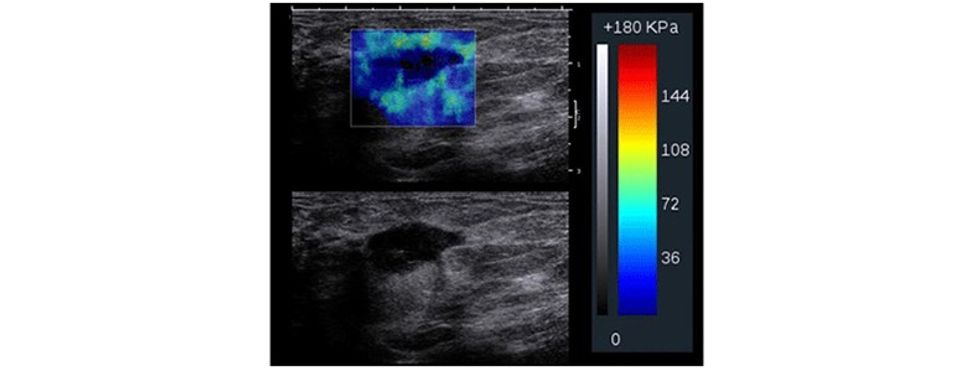

Të dhënat e fituara përpunohen përmes paketës softuerike në formë të color mapping apo grayscale për të vizualizuar zonën me interes e cila ekzaminohet.

Parimet bazë te elastografisë bazohen në dukurinë që indet nën kompresion shfaqin tendosje dhe kjo do të paraqitet me karakteristika të ndryshme. Prandaj, nën kompresion, në boshtin aksial, duke bërë matjet, mund të vlerësohet ngurtësia dhe elasticiteti i indit, para dhe pas kompresionit, ndërsa imazhi i paraqitur dhe i llogaritur quhet elastogram, ku fushat me ngurtësi të rritur dhe elasticitet të ulur paraqiten me ngjyrë të kaltër.

Indet paraqesin tendencë të ngurtësisë në ndërrimet malinje dhe imazhet rezultojnë me një kontrast me të rritur meqë kanë tendencë të ngurtësimit dhe fortësisë që rezulton me tendosje dhe ulje të elasticitetit nën kompresion të aplikuar.

Me aplikimin e elastografisë krahas ultrazërit konvencional, mundësohet që të rritet specificiteti i ultrazërit, sidomos në lezionet e kategorizuara me BiRads 4, duke bërë përcaktimin e elasticitetit të indit, detektim të qartë të nivelit të elasticitetit të indit dhe, marrë parasysh që formacionet me natyrë malinje kanë dendësi më të lartë dhe elasticitet të ulur gjatë aplikimit të kompresionit në boshtin aksial e shprehur në kPa. Pastaj me anë të mapingut qartë detektohet natyra e lezionit.